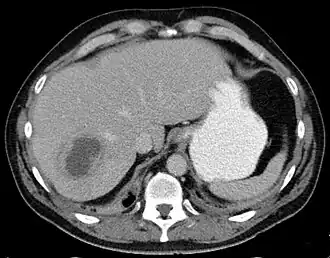

De symptomen van een leverabces omvatten gewoonlijk hoge koorts, gevoelige lever, misselijkheid en braken, geelzucht en bloedarmoede. De diagnose wordt bevestigd met behulp van echografie en een CT-scan. Complicaties van een leverabces zijn onder meer bloedvergiftiging of scheuren van de abcesholte met doorbraak in de vrije buikholte en daaropvolgende buikvliesontsteking.